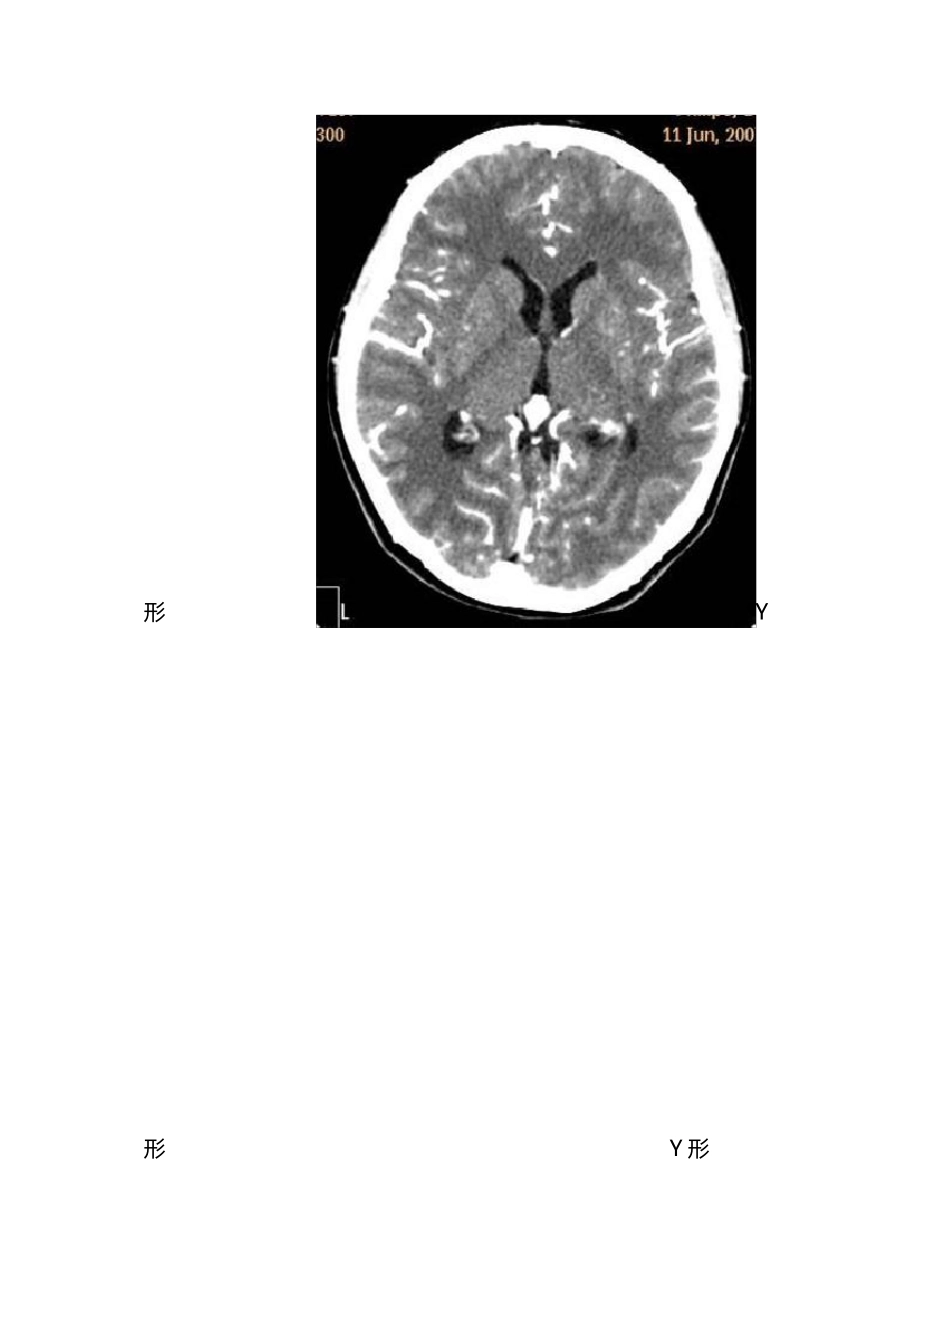

影响解剖学 知识点 学 期 结 束 了 , 在 此 把 学 的 知 识 整 理 一 下 , 这 里 有 老 师 讲 课 中 强调 的 考 试 重 点 , 也 有 以 后 到 临 床 要 注 意 的 问 题 。 这 里 不 安 书 本 的 章 节 顺序 …… 一 , 中 枢 神 经 系 统 1、颅中 窝:蝶鞍两侧从前至后 依次为眶上裂、圆孔、卵圆孔、棘孔。 (眶上裂通过动眼神 经 、滑车神 经 、三叉神 经 的 眼神 经 以 及外展神 经 , 圆孔通过上颌神 经 , 卵圆孔通过下 颌神 经 , 棘孔通过脑膜中 动脉) 2、脑干的 组成:中 脑、脑桥、延髓。 3、大脑半球比较重 要 的 三个沟:中 央沟、外侧沟、顶枕沟。 4、颅缝的 封合时间是 30—50 岁, 闭合顺 序 是矢状缝、冠状缝、人字缝。 5、鞍上池的 形状有 五边形和六边形,五边形时后 方为脑桥上缘,六边形时正后 方为脚间池,脚间池向后 通环池,四叠体池(呈“W”型)。脚间池和环池环绕的 脑组织是中 脑。 6、小脑幕的 形态: 有 八字形、V 形、Y 形 八字形 V形 Y形 Y 形 7、大脑半球从外向里的结构:脑皮质、脑髓质、基底核、第三脑室 8、 大脑大动脉环(基底动脉环):由前交通动脉、双侧大脑前动脉起始部、两侧颈内动脉、两侧后交通动脉及两侧的大脑后动脉起始部构成,又称 Willis 环. 二、头颈部 9、中耳的结构:包括鼓膜、咽鼓管、鼓室、听小骨、乳突窦,乳突小房。 10、内耳从前内到后外结构为:耳蜗、前庭、半规管 11、面神经管的分段:内耳上段、鼓室内壁段、乳突段 12、常见变异:鼓室盖低位、乙状窦前位、导静脉高位 13、窦口鼻道复合体(OMC):即前组副鼻窦在中鼻道开口区域,包括(上颌窦口、)钩突、筛漏斗、半月裂、筛泡、中鼻甲和中鼻道. 14、硬脑膜窦: 三、消化系统 15、食管的三个狭窄、三个压迹的名称 三 个 狭 窄 : 第 一 狭 窄 : 位 于 食 管 与 咽 的 连 接 处 , 距中 切 牙 15cm。 第 二 狭 窄 : 位 于 食 管 与 左 支 气 管 交 叉 处 , 距 中切 牙 25cm。 第 三 狭 窄 : 位 于 食 管 穿 膈 肌 处 ( 通 过 食 管 裂 孔处 ) , T10 水 平 , 距 中 切 牙 40cm。 三 个 压 迹 : 主 动 脉 弓 压 迹 、左 主 支 气 管 压 迹 、左 心房压 迹 ( 最长最浅)...